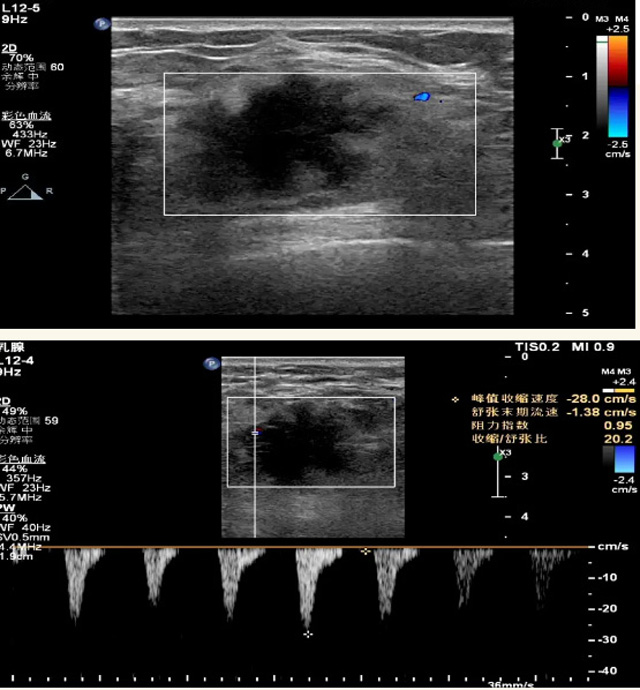

乳腺B超檢查無輻射,對囊性病變敏感,可以實時觀察病灶。超聲引導活檢跟手術前的定位。就是它對于微小的鈣化查出率比鉬靶稍微差點。磁共振MRI檢查也是是沒有輻射的,對備孕跟已經懷孕的人士比較友好。不用擔心這個輻射影響胎兒問題。對乳腺病灶敏感性較高,致密乳腺病灶、乳腺癌的復發,準確鑒別囊性及實性病變??梢詭椭R床醫生判斷惡性、良性病變。但是MRI磁共振對微小鈣化不明顯,微鈣化還是鉬靶靠譜點。檢查時間比較長,有偽影的影響。費用相對B超,鉬靶高很多。

乳腺B超